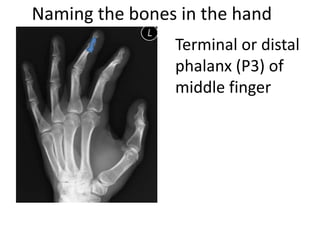

This document provides an overview of hand anatomy including:

- Naming the bones, joints, tendons, nerves and skin landmarks of the hand and wrist.